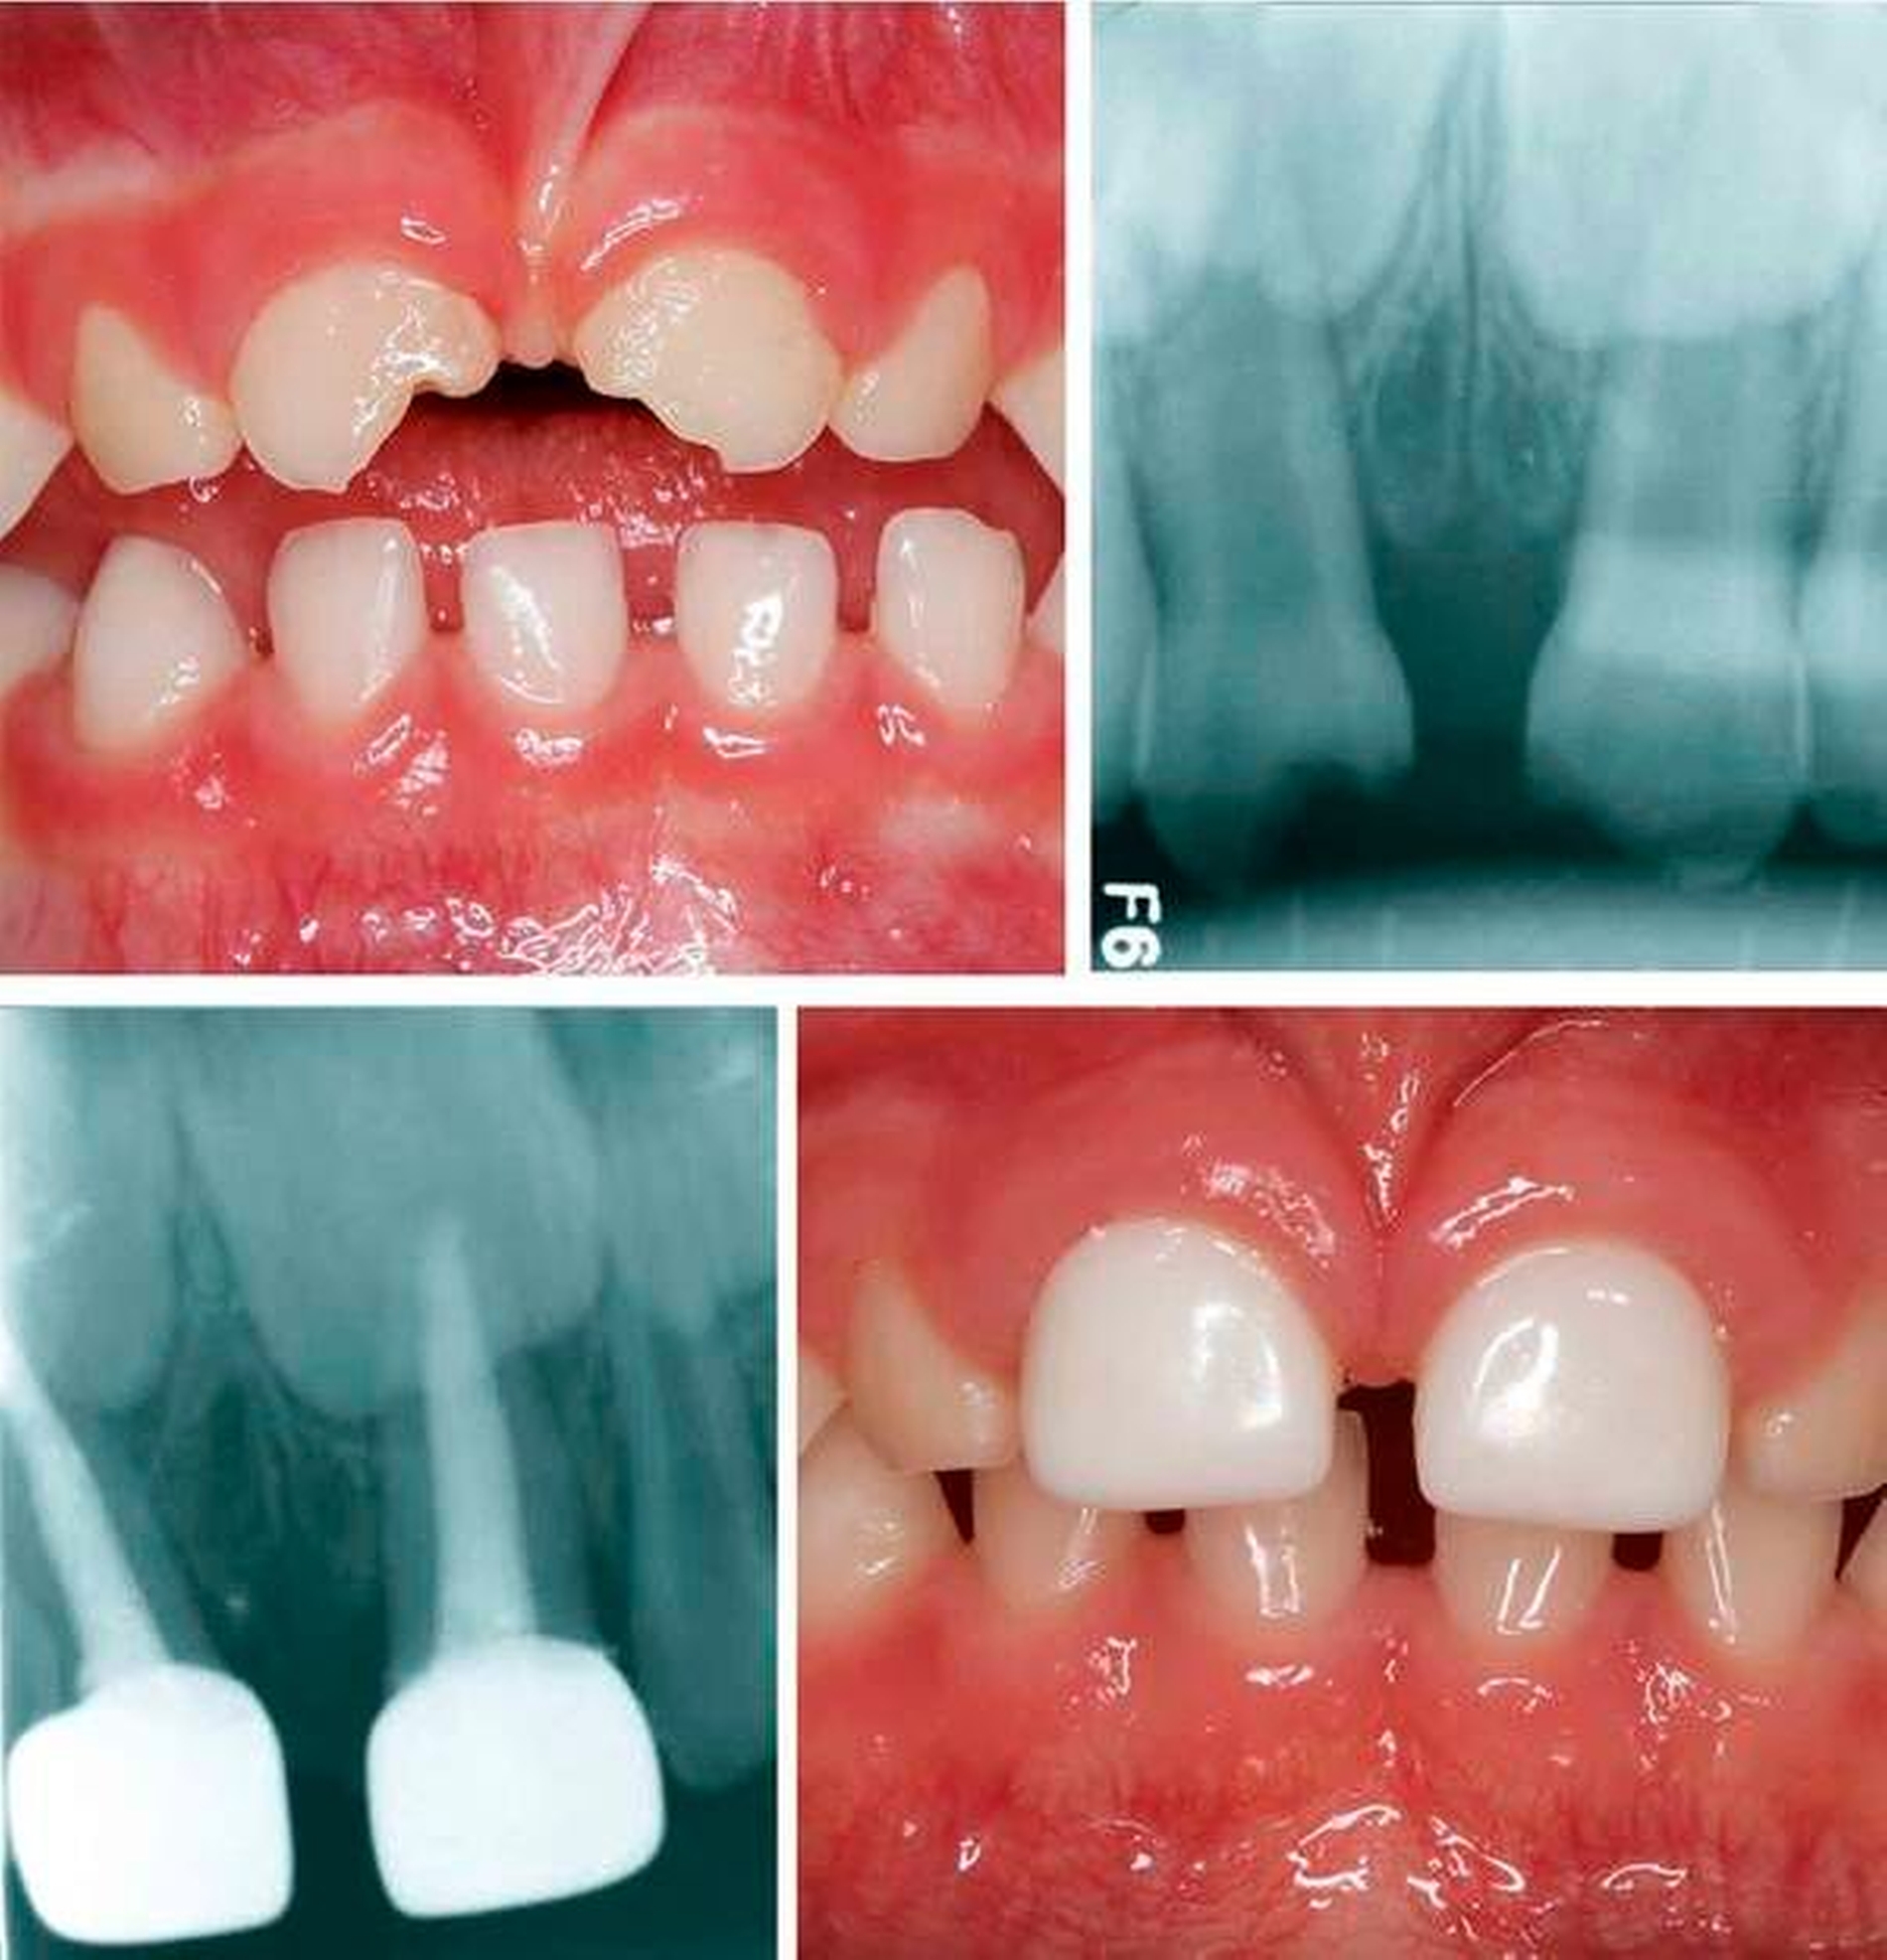

Um den Erhalt der Oberkieferfrontzähne bei der Nuckelflaschenkaries oder nach Frontzahntrauma einzuschätzen, hat sich der Aufbiss bewährt. Falls das Kind den Mundfilm nicht toleriert, stellt das Orthopantomogramm keine Alternative zur exakten Diagnostik dar und sollte nur im Ausnahmefall, zum Beispiel bei Verdacht auf eine Durchbruchstörung, Verlagerung, allgemeines Trauma oder Molaren-Inzisivi-Hypomineralisaton Anwendung finden. Zudem kann über die Akzeptanz des Röntgens die generelle Compliance getestet werden. Scheitert eine intraorale Aufnahme, so ist auch die Compliance für eine Füllung oder gar eine Krone nicht gegeben.

Die Aufbereitung dient der Entfernung der Bakterien und des infizierten Pulpagewebes. Ein großflächiger Abtrag von infiziertem Dentin ist hingegen nicht gewünscht. Zudem sind bei jungen Kindern die Kanalwände sehr dünn, so dass eine forcierte mechanische Kanalreinigung Perforationen hervorrufen kann. Zur chemischen Aufbereitung haben sich Natriumhypochlorid aufgrund seiner gewebsauflösenden und antibakteriellen Eigenschaften sowie Kochsalz als Abschlussspülung bewährt. Nach Trocknung des Kanalsystems mit Papierspitzen wird im Idealfall eine resorbierbare Kalziumhydroxid-Jodoform-Paste (zum Beispiel Vitapex, Neo Dental International Inc, Kanada) mit leichtem Druck eingebracht und der Zahn nach Anfertigung eines Röntgenkontrollbilds mit einer Krone versorgt [AAPD, 2017]. Die Wurzelfüllung des Michzahns wird zumeist zum Erhalt der Oberkieferfrontzähne durchgeführt (Abbildung 8). Aber auch im Seitenzahnbereich ist dieser Eingriff sinnvoll, vor allem bei sehr jungen Kindern, bei denen ein frühzeitiger Zahnverlust vermieden werden soll (Abbildung 9).

Da für viele Eltern die Ästhetik eine zunehmend größere Rolle spielt, haben in den vergangenen Jahren vorgefertigte pädiatrische Zirkoniakronen (NuSmile, USA), für den Front- und Seitenzahnbereich den Dentalmarkt erobert [Waggoner, 2015]. Somit gelingt es auch, die von der Flaschenkaries geschädigten Frontzähne zu erhalten und dem Kind wieder ein strahlendes Lächeln zu schenken (Abbildung 12). Die Anpassung der Zirkoniakronen ist invasiver und zeitaufwendiger als die von Stahlkronen und der Materialaufwand ist deutlich höher. Dadurch ist diese Form der Versorgung mit Privatkosten für die Patienteneltern verbunden. Vermutlich wird diese Therapieoption deshalb vorrangig von spezialisierten Kollegen angeboten.